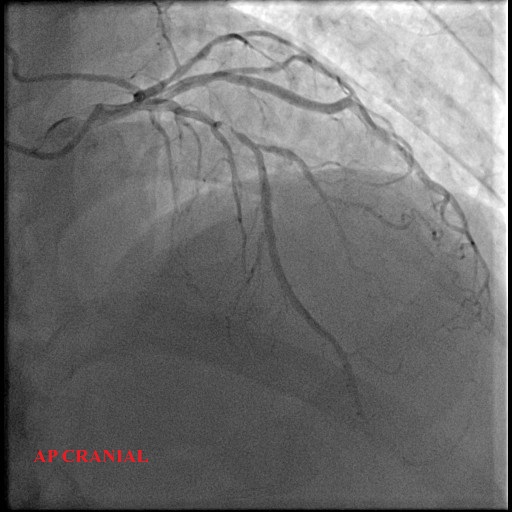

Left Main: moderate distal stenosis 40%

LAD: severe stenosis proximal 95%, TIMI 3

LCx: Small, non-dominant, diffuse disease

RCA: mild proximal disease 20%

ap cranial.avi